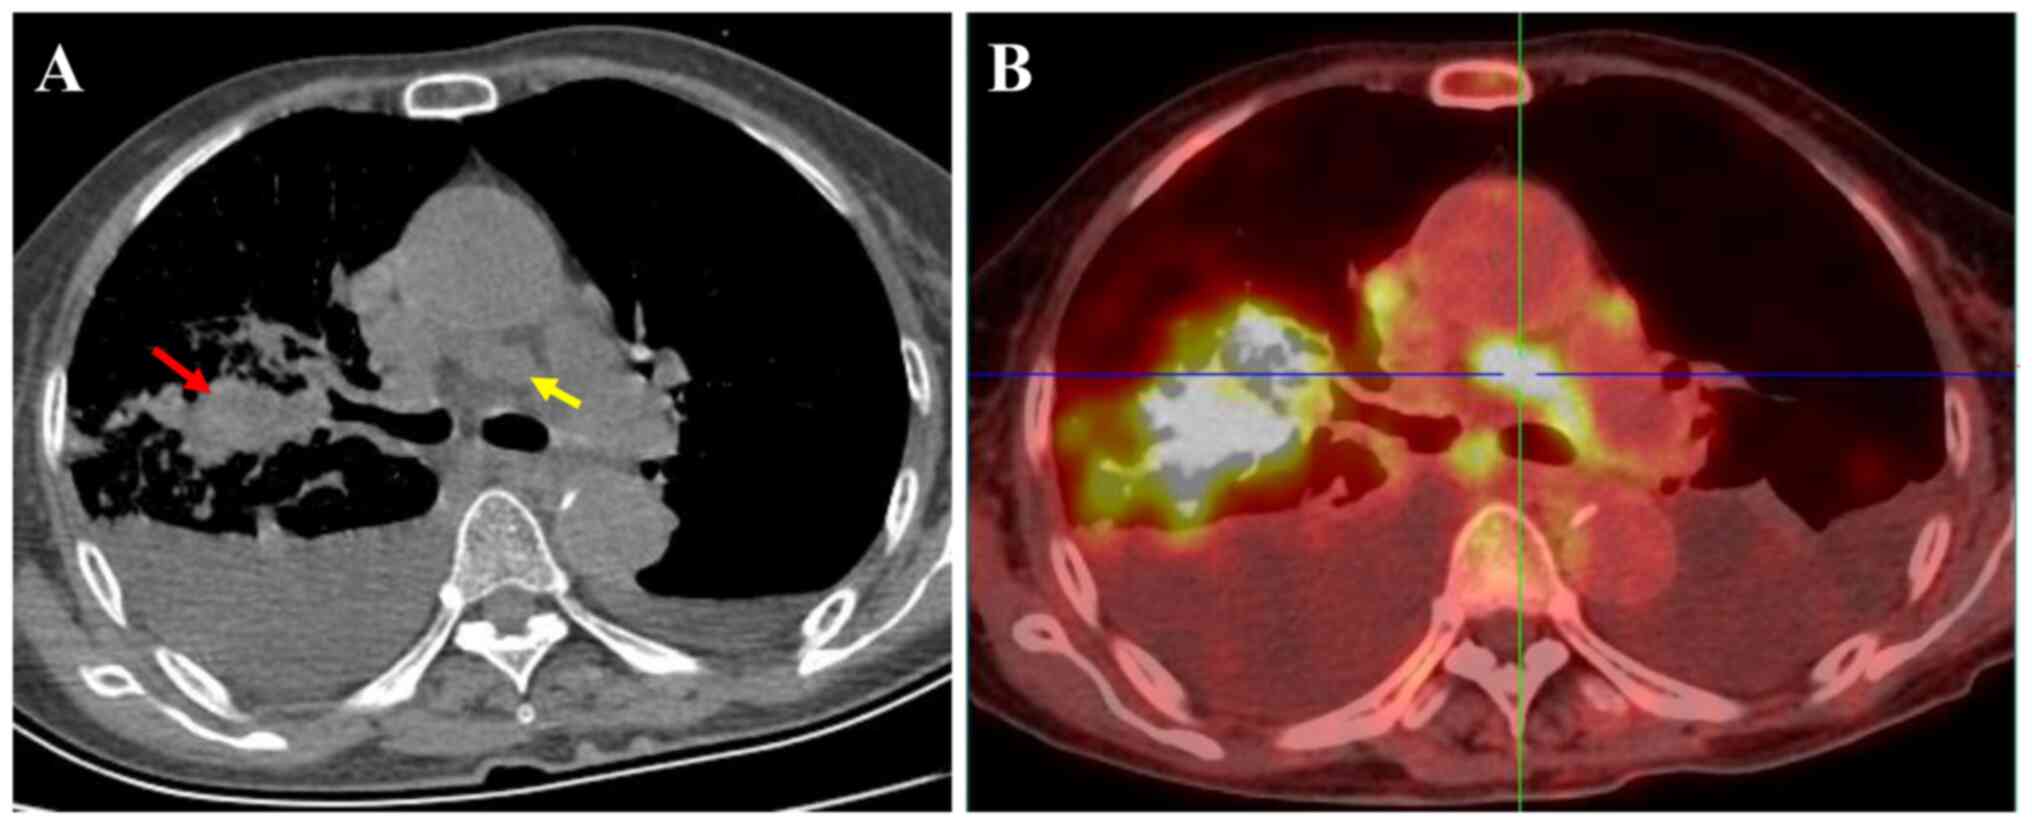

A 72-year-old non-smoking female presented to Taihe Hospital (Shiyan, China) after experiencing a 2-week history of cough and expectoration. The patient denied a prior history of skin, ear or ocular lesions. Physical examination showed percussive dullness of the right upper lung and decreased breath sounds; no nevus, hemorrhoids or pigmentation was observed on the skin, eyes, perianal or external genitals. Laboratory tests reported that the patient's carcinoembryonic antigen, cytokeratin 19 fragment, neuron-specific enolase and squamous cell carcinoma antigen levels were 1.79 µg/l (normal, 0–5.0 µg/l), 1.31 ng/ml (normal, 0–3.3 ng/ml), 10.8 ng/ml (normal, 0–16.3 ng/ml) and 0.58 ng/ml (normal, 0–2.7 ng/ml), respectively. Chest X-ray indicated an irregular mass in the upper lobe of the right lung with a rough margin. Chest CT showed a solid mass with a size of 2.1×3.9×3.0 cm in the upper lobe of the right lung, with a CT value of 56 HU. Multiple enlarged lymph nodes with a short diameter of 1.4 cm were observed in the mediastinum and bilateral pleural effusion was found (Fig. 1A). Thoracentesis cytology using hematoxylin and eosin staining showed that lymphocytes and mesothelial cells were predominant and there was no evidence of malignancy. Bronchoscopy showed an endobronchial mass in the right main bronchus (Fig. 2A), and the local mucosa in the distal bronchus of the right upper lobe was rough, hypertrophic and gray-black (Fig. 2B). Transbronchial forceps biopsy of the mass was performed and rapid on-site evaluation (ROSE) identified this as MM (Fig. 3A and B). Based on the preliminary ROSE diagnosis, endobronchial ultrasound-guided transbronchial needle aspiration (EBUS-TBNA) was performed directly for staging of the lung cancer during the procedure.

Figure 1.

Diagnostic chest imaging. (A) Chest computed tomography scan showed a mass in the right upper lobe (red arrow) and enlargement of mediastinal lymph nodes (yellow arrow). (B) Positron emission tomography revealed a lung mass with a SUVmax of 24.7 and enlarged mediastinal lymph nodes with a SUVmax of 15.9. SUVmax, maximum standardized uptake value.

Immunohistochemistry was performed using the aforementioned biopsy sections. Sections were heated at 65°C for 120 min and then dewaxed by incubation with xylene for 3 min (six times). Sections were rehydrated using a decreasing alcohol series and antigen repair was performed using EDTA repair solution (pH 9.0; Fuzhou Maixin Biotech Co., Ltd.) by heating in a pressure cooker to boiling and then being kept warm for 20 min. Sections were incubated with 3% H2O2 for 10 min and then rinsed with PBS for 3 min to block endogenous peroxidase activity. Sections were incubated with ready-to-use primary antibodies against HMB45 (cat. no. MAB-0098; Fuzhou Maixin Biotech Co., Ltd.), SOX-10 (cat. no. MAB-0726; Fuzhou Maixin Biotech Co., Ltd.), S-100 (cat. no. Kit-0007; Fuzhou Maixin Biotech Co., Ltd.), Melan-A (cat. no. JY-0083; Dako; Agilent Technologies, Inc.) and Ki-67 (cat. no. JY-0222; Dako; Agilent Technologies, Inc.) for 1 h at room temperature. Washing was performed using PBS. Sections were then incubated with EnVision Detection Systems Peroxidase/DAB, Rabbit/Mouse (cat. no. K5007; ready-to-use; Dako; Agilent Technologies, Inc.) secondary antibodies for 30 min at room temperature. DAB from the aforementioned secondary staining kit was added for detection. Sections were counterstained with hematoxylin for 2 min at room temperature and imaged using a CX31 light microscope (Olympus Corporation). Immunostaining revealed melanin pigmentation and malignant cells that were positive for HMB-45, Melan-A, SOX-10, S-100 and Ki-67 (>20%) and negative for CKAE1/AE3 (cat. no. JY-0047), CK5/6 (cat. no. MAB-0744), TTF-1 (cat. no. MAB-0677), CD-45 (cat. no. Kit-0024) and synaptophysin (cat. no. MAB-0742) (all ready-to-use; Fuzhou Maixin Biotech Co., Ltd.) (Fig. 4). Whole-body 18F-FDG PET-CT revealed a density anomaly in the mass in the right upper lung complicated by elevated glucose metabolism with a maximum standardized uptake value (SUVmax) of 24.7 and elevated glucose metabolism of the hilar/mediastinum lymph nodes with an SUVmax of 15.9 (Fig. 1B). There were multiple metastatic lesions in the kidney, liver and bones. On the 10th day following admission, genetic molecular testing for BRAF or NRAS mutations using PCR-Sanger sequencing was performed by the Clinical Molecular Diagnostic Center of Taihe Hospital, Hubei University of Medicine, and a BRAF V600E mutation was reported (Table I). Dabrafenib (150 mg orally twice daily) plus trametinib (2 mg orally once daily) was subsequently administered, and following 2 months of therapy, a chest contrast-enhanced CT scan revealed that the malignant melanoma mass in the right lung had markedly reduced in size (Fig. 5). The patient was followed up, 15 months to date, and remained in good health with no evidence of recurrence. However, close follow-up of the patient is ongoing.